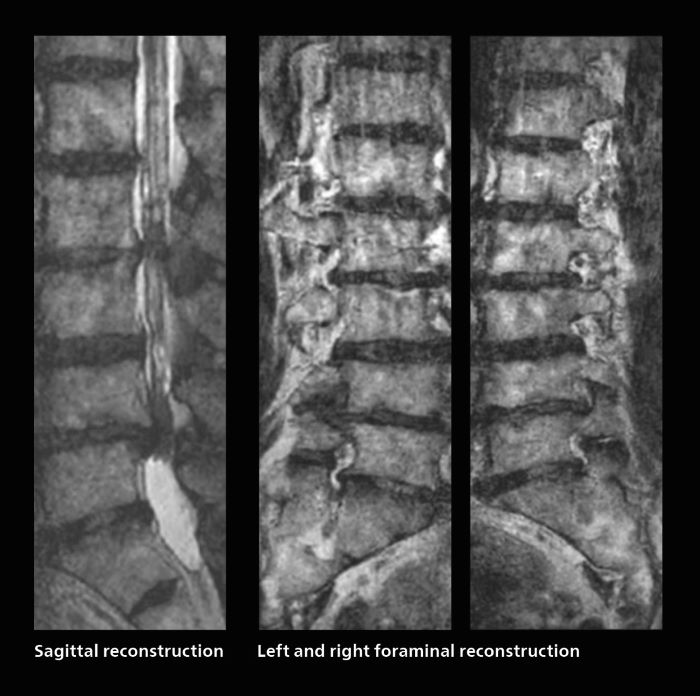

Faster lumbar spine exams are beneficial for patients with pain

Many patients who must undergo a lumbar spine examination suffer from back pain. For these patients it is difficult to maintain the imaging position long enough to successfully complete the examination. “In such cases, using SmartSpeed allows us to perform volume imaging, so that we acquire only one high resolution 3D sequence in a short time and then reconstruct the other orientations from that,” Dr. Katahira says. “This is highly advantageous because the patient needs only endure a short exam time, whereas before it was necessary to acquire a larger number of sequences in total. We have seen that the shorter time has allowed us to scan patients who previously could not finish the exam. This is a great advantage.”

Fast lumbar spine imaging for successful exam of patient in pain

A patient arrived saying that undergoing MRI was not possible because of severe back pain and leg pain, was imaged with SmartSpeed in only 94 seconds. The scan was diagnostic and afterwards the patient confirmed that it only took a little while. Performed on Elition X.

The hospital’s fast lumbar spine ExamCard includes T2W SpineVIEW, 1:40 min, 1.0 mm isotropic, acceleration factor 12.